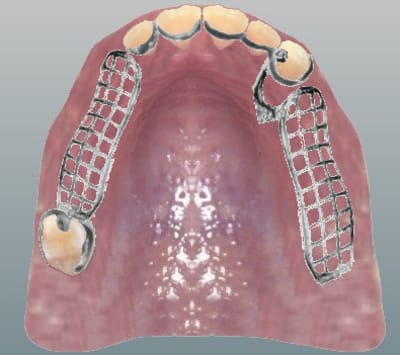

@steph94 : voici le tracé de mon futur châssis (cf PJ - je ne sais pas encore quelle forme donner à ma plaque base..)